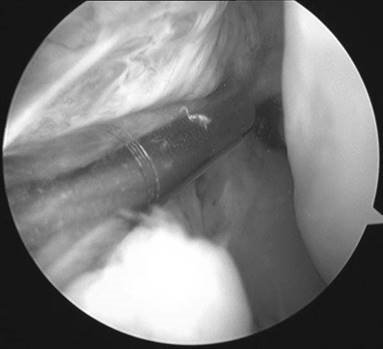

What does his arthroscopy picture show?

The limited view shows a bare lateral wall of the femoral notch, in keeping with a complete ACL rupture.